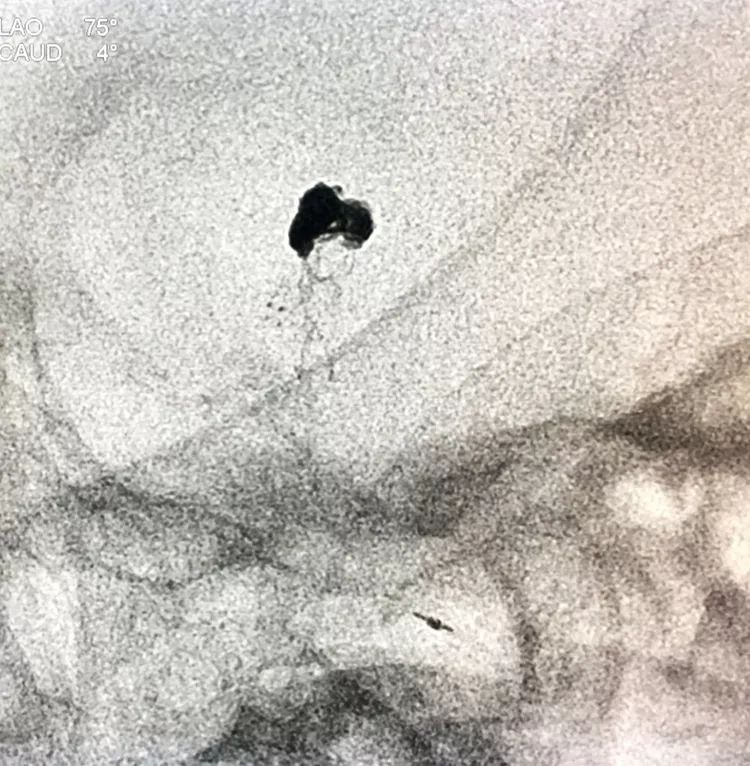

工作位造影看动脉瘤栓塞满意,子瘤已不显影,是不是可以收手了呢?

旋转增强器透视观察各个投照角度弹簧圈的分布情况,侧位透视发现瘤腔后部的弹簧圈分布疏松,形成死腔,看来革命还未成功,同志尚需努力呀!

回头再观察左椎动脉造影的三维成像,发现瘤腔确实有向后方突出的分叶,明确弹簧圈团后部的空虚处仍是瘤腔的一部分